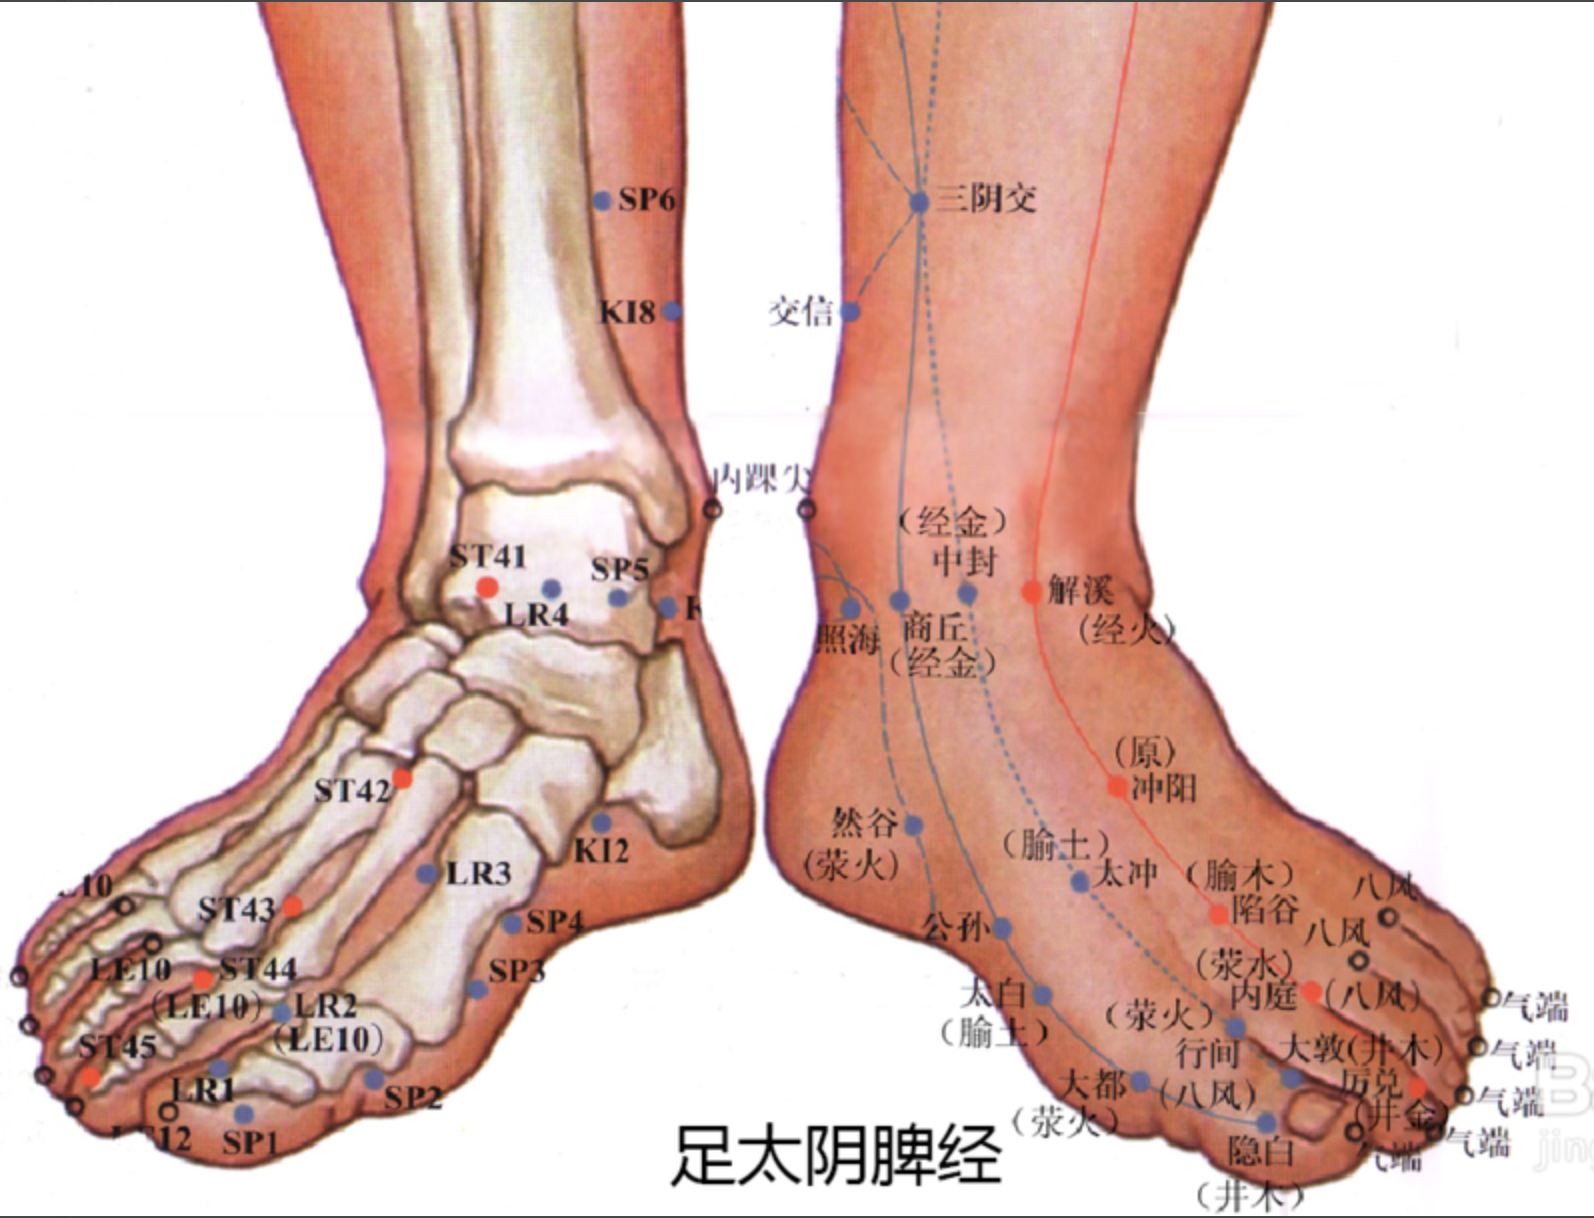

隐白

【定位】 在足大趾末节内侧,距趾甲角 0.1 寸(图 10-22-2)。

【主治】 腹胀,便血,尿血,月经过多,崩漏,癫狂,多梦,惊风。

【配伍】 配地机、三阴交治疗出血症。

【刺灸法】 浅刺 0.1 寸。

【附注】 足太阴经所出为“井”。

公孙

【定位】 在足内侧缘,当第 1 跖骨基底部的前下方(图 10-22-2)。

【主治】 胃痛,呕吐,腹痛,泄泻,痢疾。

【配伍】 配中脘、内关治胃酸过多、胃痛。

【刺灸法】 直刺 0.6 ~ 1.2 寸。

【附注】 足太阴经络穴:八脉交会穴之一,通于冲脉。参考资料:①据报道,对消化性溃疡病人进行 X 线胃肠检查时,观察到针刺内关、足三里对胃蠕动多有增强作用,尤以足三里为明显,而针刺公孙则胃蠕动多减弱。②据报道,针刺公孙、内关、梁丘等穴有抑制胃酸分泌作用。

三阴交

【定位】 在小腿内侧,当足内踝尖上 3 寸,胫骨内侧缘后方(图 10-22-3)。

【主治】 肠鸣腹胀,泄泻,月经不调,带下,阴挺,不孕,滞产,遗精,阳痿,遗尿,疝气,失眠,下肢痿痹,脚气。

【配伍】 配足三里治肠鸣泄泻,配中极治月经不调,配子宫治疗阴挺,配大敦治疝气,配内关、神门治失眠。

【刺灸法】 直刺 1 ~ 1.5 寸。

【附注】 (1)足太阴、少阴、厥阴经交会穴。(2)孕妇禁针。